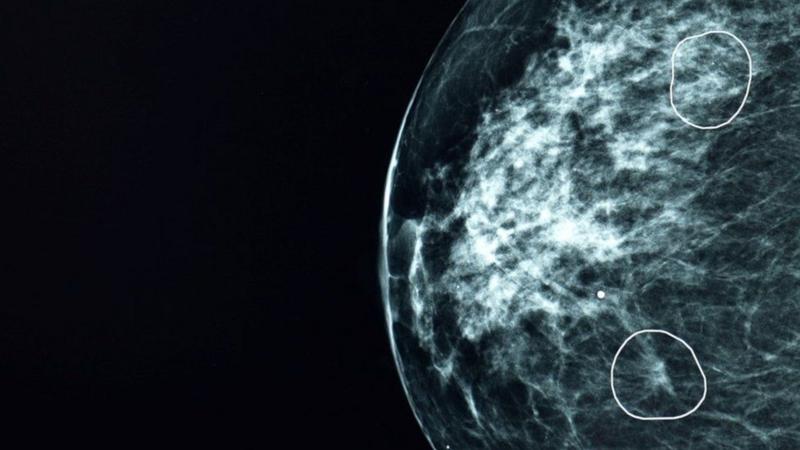

هوش مصنوعی سرطان پستان ۱۱ زن را تشخیص داد که از چشم پزشکان دور مانده بود

🔹یک مرکز بیمارستانی در اسکاتلند با هوش مصنوعی نشانههای ناپیدای سرطان پستان را که از از چشم پزشکان دور مانده بودند، در ۱۱ زن تشخیص داد. این فناوری هوش مصنوعی برای تشخیص سرطان پستان که میا نام دارد، در یک برنامه آزمایشی در کنار پزشکان برای بررسی ماموگرافی بیش از ده هزار زن به کار گرفته شد که بیشترشان سرطان نداشتند. میا نه فقط با موفقیت همه کسانی را که علائم سرطان داشتند شناسایی کرد، بلکه ۱۱ زن را هم پیدا کرد که سرطانشان از چشم پزشکان مخفی مانده بود./بی بی سی